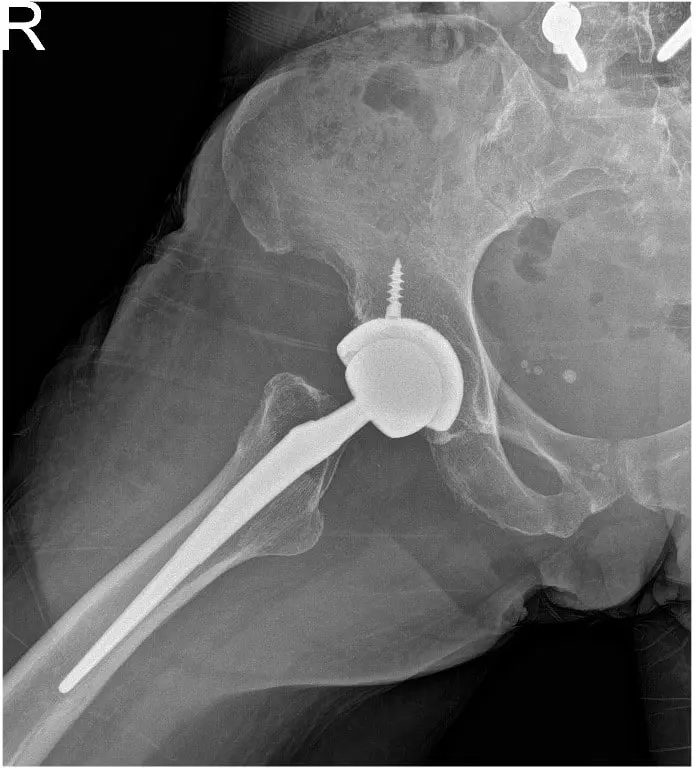

Bilateral Total Hip Replacement in a 65 yr old female

Post operative view xray of the hip